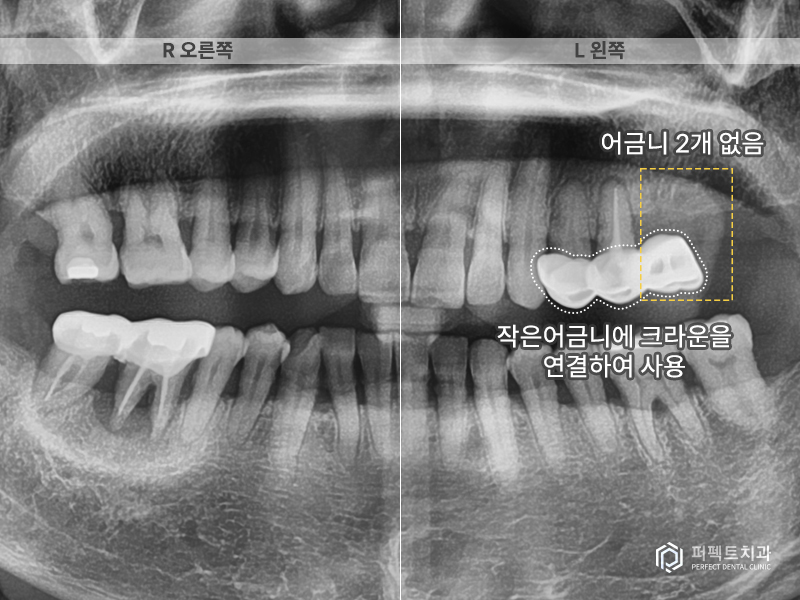

그리고 왼쪽에도 문제가 있는 치아가 있는데 이 곳은 어금니 두개가 없고 앞에 작은 어금니 두개를 이용해서 달려있는 치아를 하나 만들어 오랫동안 사용하고 있는 상황이었습니다. 결국 치아 두개가 없는 경우이기 때문에 앞에 치아가 무리하게 힘을 받아 앞에 있는 치아까지 망가진 경우라고 생각하시면 됩니다.